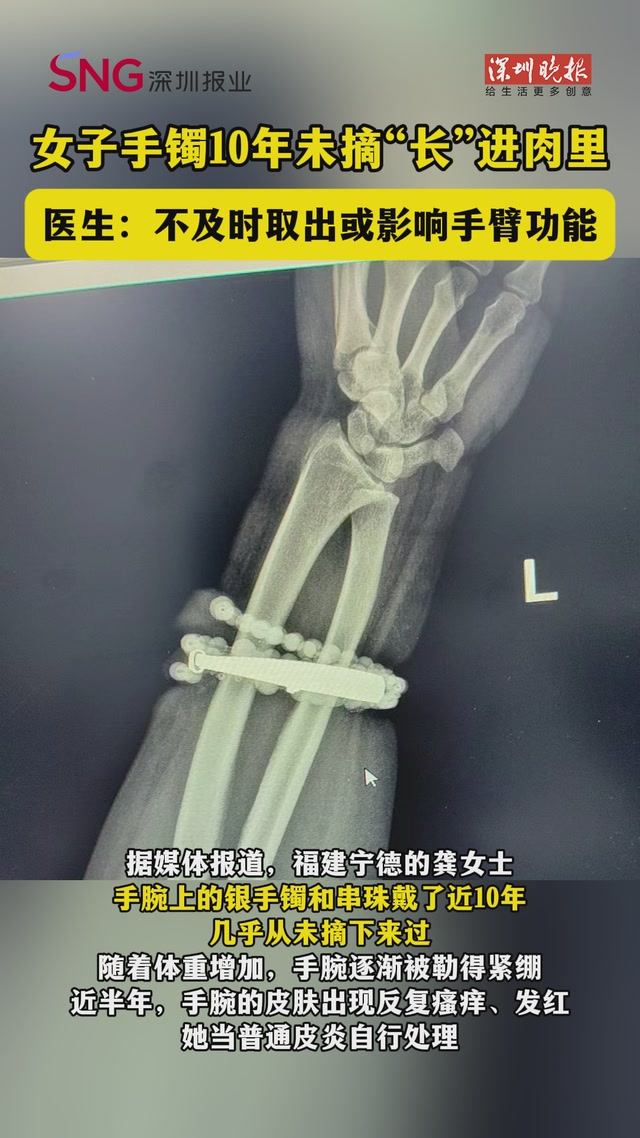

• 女子手镯10年未摘“长”进肉里!医生:不及时取出或影响手臂功能

女子手镯10年未摘“长”进肉里!医生:不及时取出或影响手臂功能